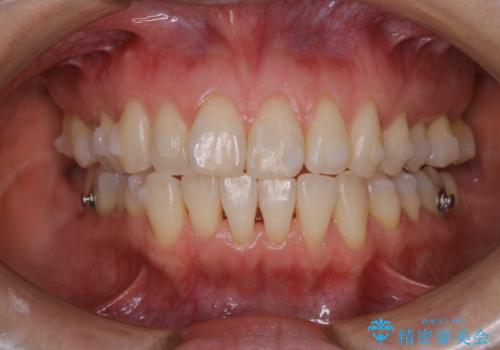

矯正治療終了後にPMTC(Professional Mechanical Tooth Cleaning)

担当医 歯科衛生士